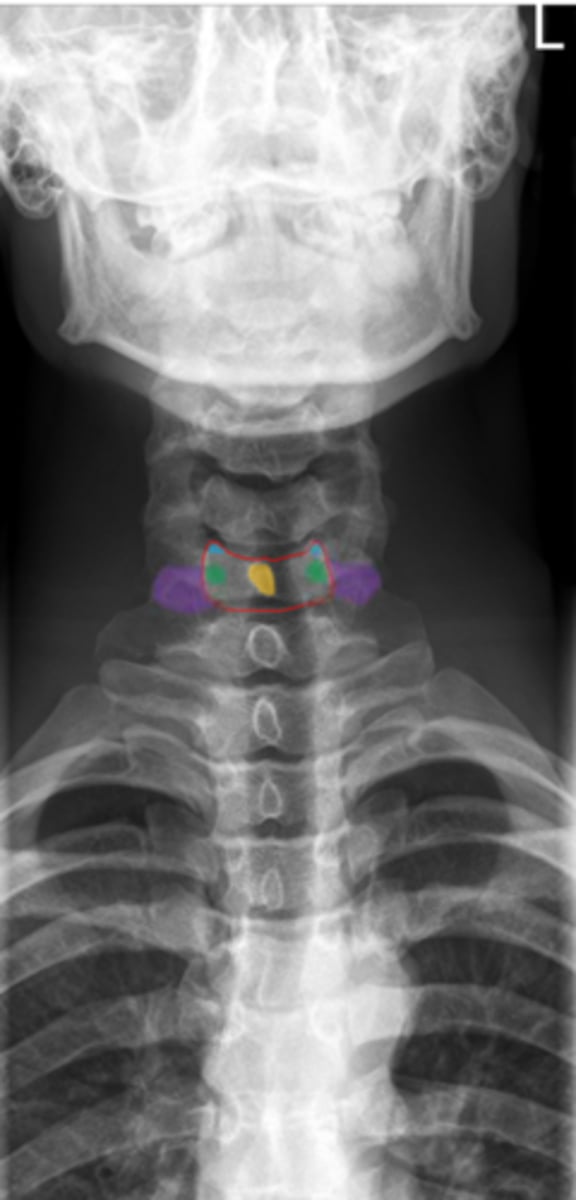

uncinate process

Identify the blue structure

transverse process

Identify the purple structure

pedicles

Identify the green structure

spinous process

Identify the yellow structure

C1 and C2

What vertebrae is being examined?

Odontoid process (dens)

Identify the purple structure

anterior arch/tubercle

Identify the red structure

posterior arch/tubercle

Identify the green structure

lateral masses

Identify the blue structure